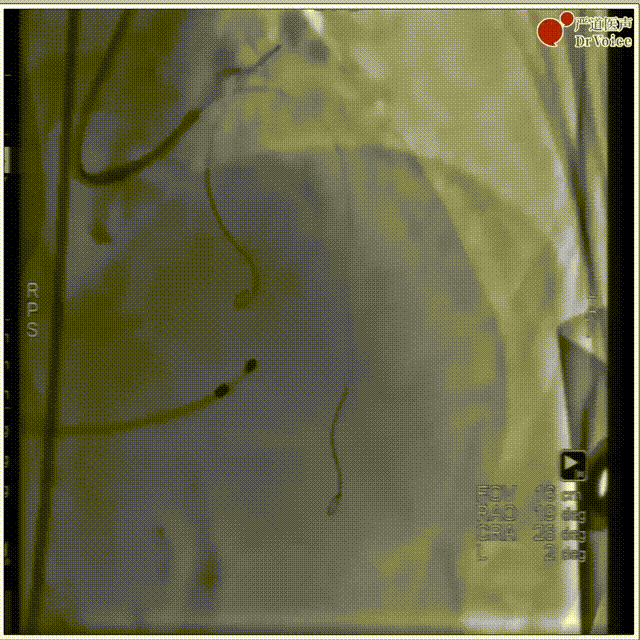

1. 冠脉造影。

冠脉造影图片1

冠脉造影图片2